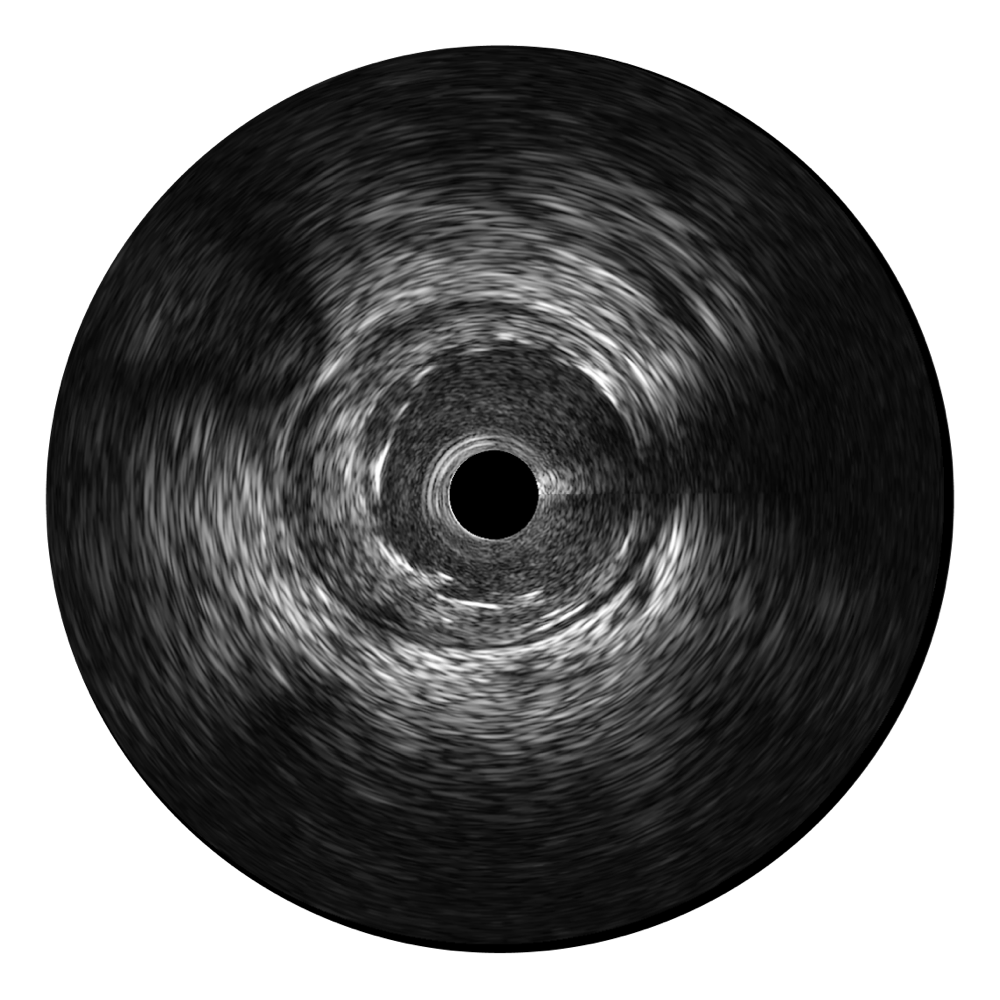

• 环球UG官网宽频IVUS图像

• 传统IVUS图像

对比传统IVUS导管成像,环球UG官网宽频IVUS图像的近场支架梁显影更细腻,远场中膜外血管仍清晰可辨,兼顾远中近,兼顾分辨力与穿透深度